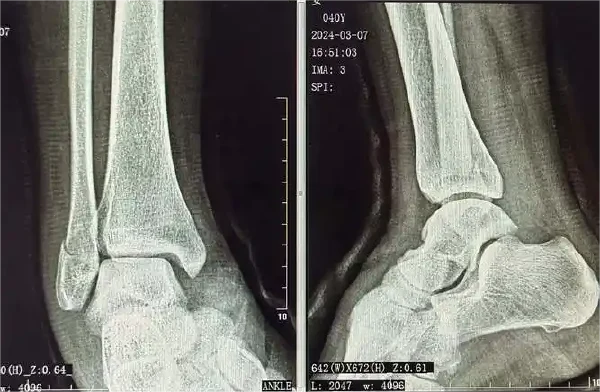

影像学检查是确诊骨折的金标准。X光片是最常用的检查方法,能够清晰显示骨折的部位、类型和程度。对于一些复杂骨折或怀疑合并有软组织损伤的情况,CT扫描和MRI检查则可以提供更详尽的信息。

评估方面,医生通过体检、影像学检查以及功能测试来评估骨折的愈合情况和恢复情况。体检包括触诊、观察以及活动范围评估。影像学检查尤其是X光片和CT扫描可以显示骨折愈合的情况以及是否存在移位。功能测试则是通过评估患者的行走、负重、踝关节活动度等功能来了解恢复程度。